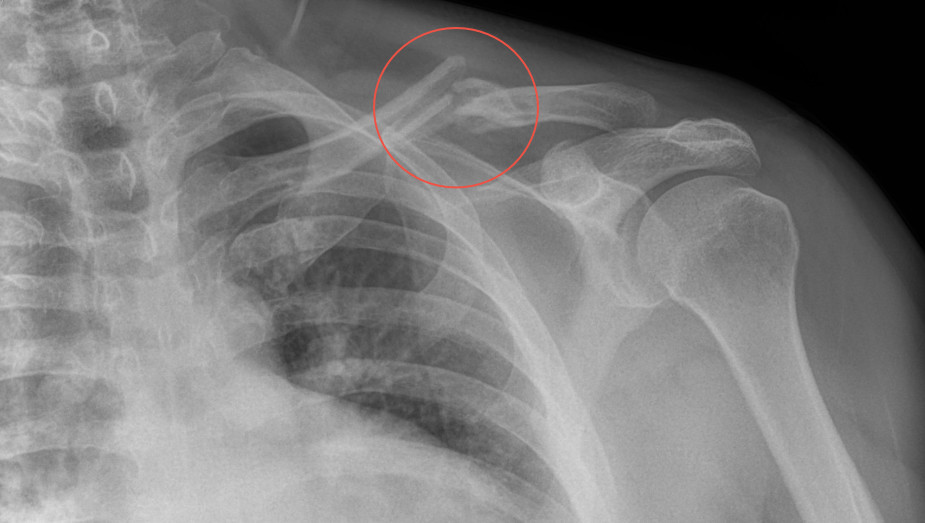

Desde el descubrimiento de los rayos “X” y las placas radiográficas por Wilhelm Conrad Roentgen y su posterior difusión a través de la Asociación Físico médica de Wurzburg el 28 de diciembre de 1895, que fue la primera asociación que habló de los nuevos rayos que podían penetrar el cuerpo y fotografiar los huesos, ha habido muchos cambios tanto en la forma de obtener, procesar e incluso en la forma de visualizar, manejar y almacenar las placas radiográficas.